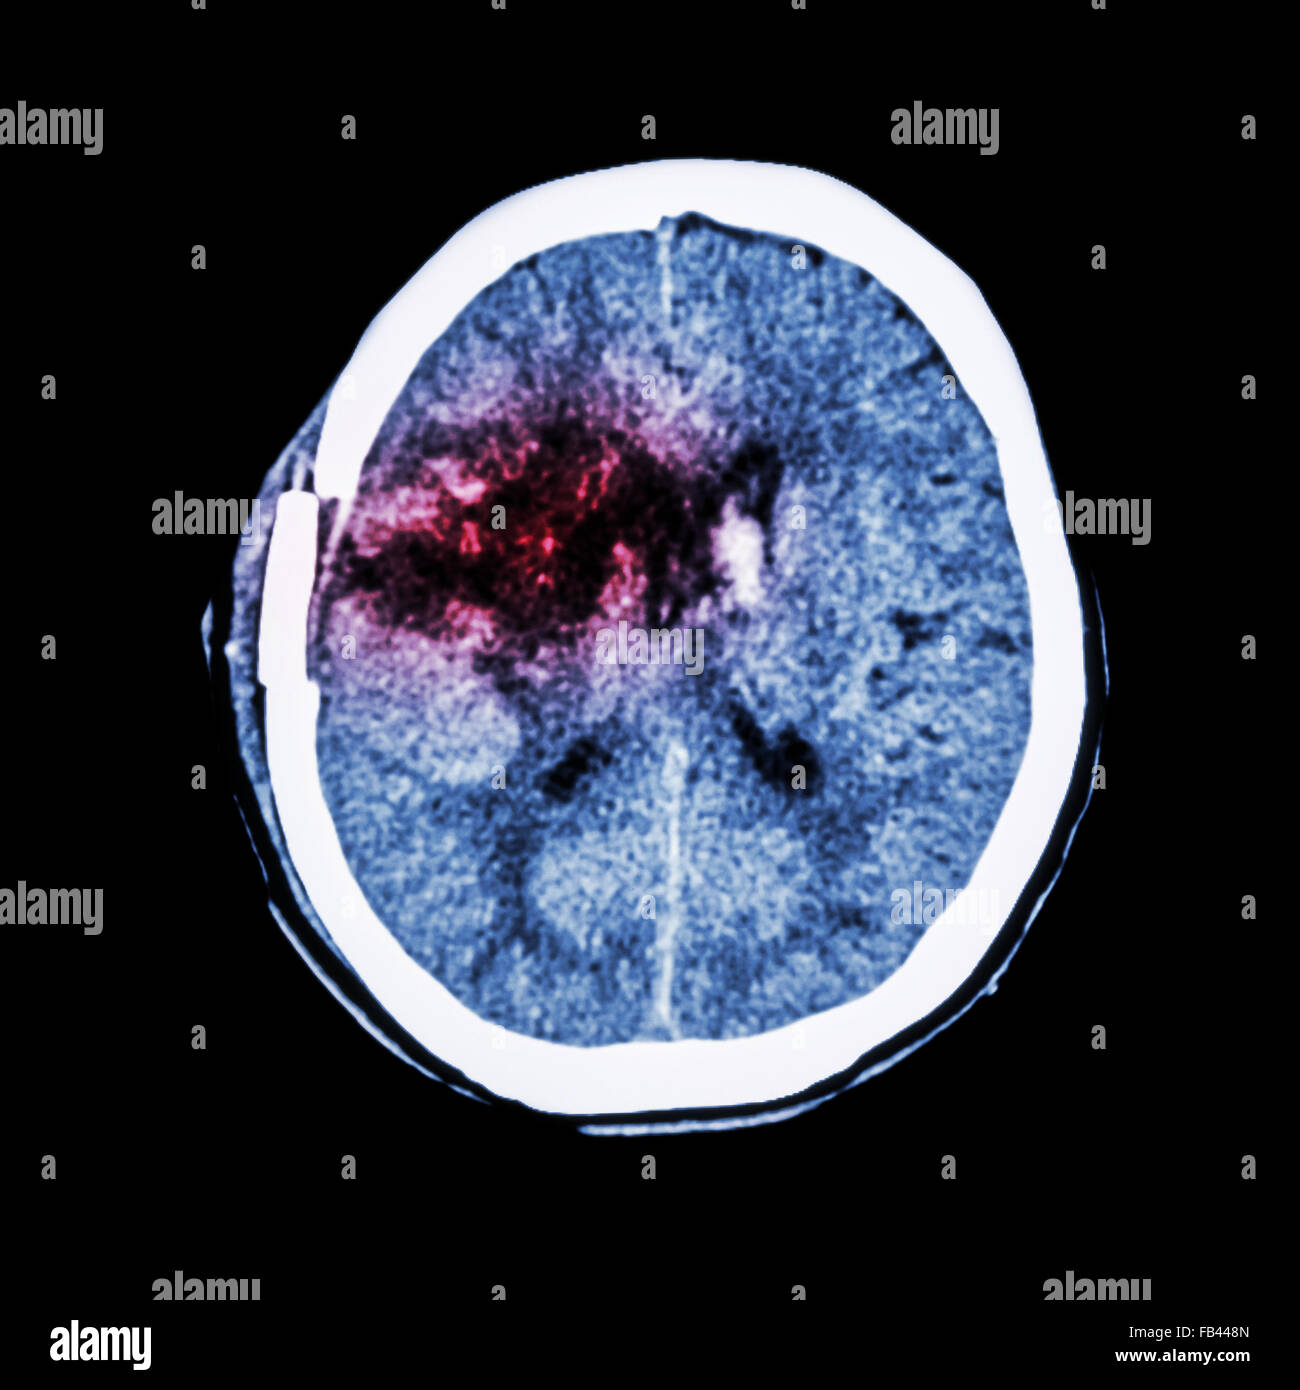

From stock.adobe.com

thrombosis basal ganglia cancer Brain traumatic injury and High blood Basal Ganglia Bleed Hemorrhage in the basal ganglia causes contralateral hemiplegia and a gaze preference to the side of the bleeding owing to. Find out what causes a. When this is severely impacted the term “abulia” is used to describe the deficits. Learn about the causes, clinical features, and treatment of basal ganglia hemorrhage, one of the most severe strokes. Find out the. Basal Ganglia Bleed.